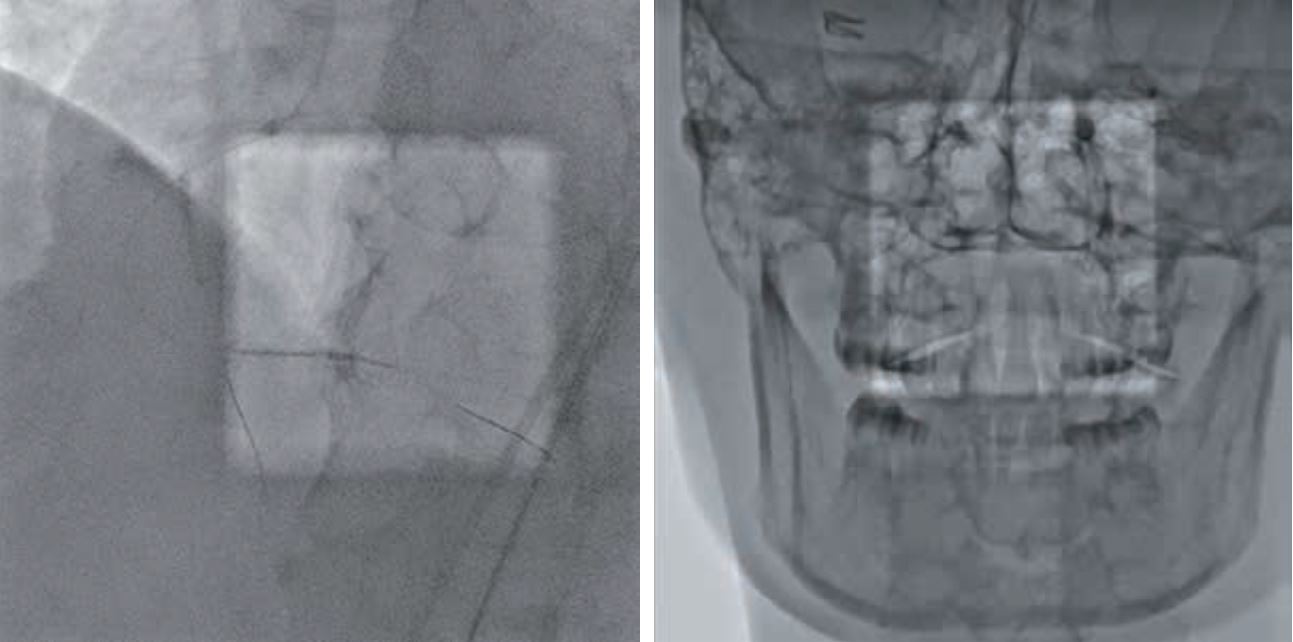

· Dose Tracking System (DTS) – Система стеження за дозою обраховує та відображає в реальному часі дозу на шкіру, отриману пацієнтом. У разі досягнення попередньо заданого критичного рівня дози така система попередження допомагає лікарям уникнути ризику променевого ураження шкіри за рахунок зміни проекції, SID, частоти кадрів.